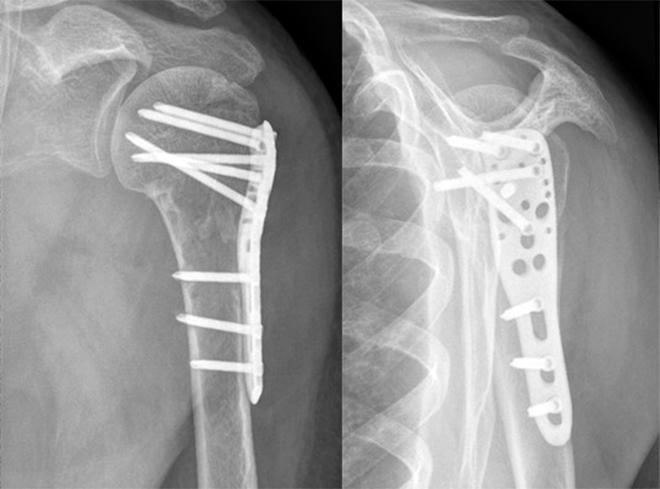

Что касается остеосинтеза предплечья, то существуют также различные варианты:

- Штифты внутреннего типа (устанавливаются в костную ткань);

- Винты, болты и пластины металлического типа (винты устанавливаются непосредственно в костную ткань, пластины на костную поверхность);

- Проволока или металлическая нить (проводятся через канал костного типа).

Выбор варианта синтеза осуществляется исключительно на основании детальной оценки ситуации, локализации перелома, его характера, состояния пациента.